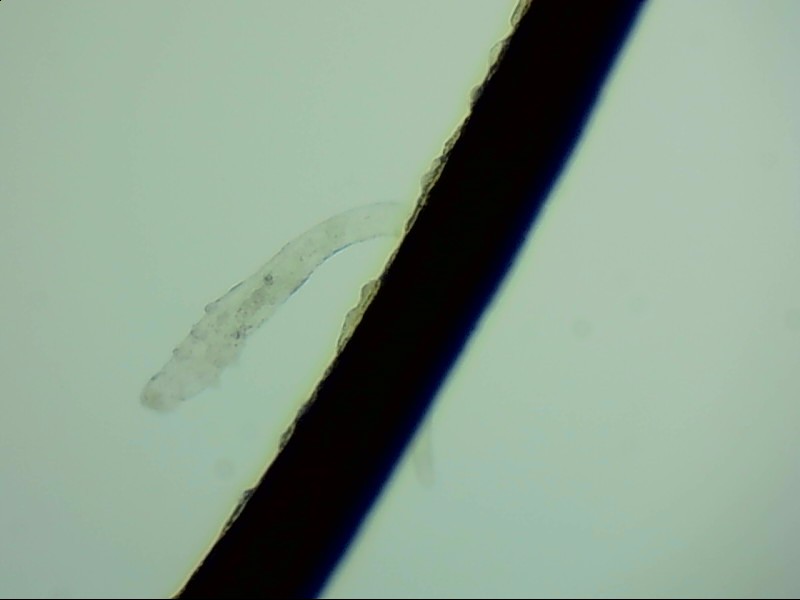

眼睛里的蛔蟲

蛔蟲是我們聽聞最多的一種寄生蟲,它的出現(xiàn)往往帶著腸道、發(fā)育不良等字眼。但誰能想到,蛔蟲不但生活在腸道里,它還會在器官中移動,甚至進(jìn)入眼睛。